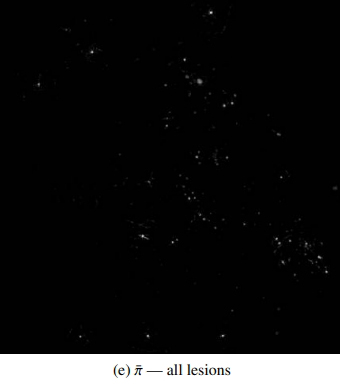

Fond d’œil et détection des lésions liées à la rétinopathie diabétique par l'algorithme de Ophtai, Instant automatic diagnosis of diabetic retinopathy, G Quellec, M Lamard et al. (2019) ©DR

Ces dernières décennies, l’imagerie en ophtalmologie a connu une véritable révolution avec le développement de nouvelles techniques de pointe, l’amélioration de la résolution d’image et l’arrivée de l’intelligence artificielle. L’intelligence artificielle est aujourd’hui de plus en plus utilisée pour aider au diagnostic et transforme la pratique des ophtalmologistes, surtout dans un contexte de difficultés d’accès aux soins. Grâce au deep learning (apprentissage profond), qui donne aux machines la capacité d’apprendre à partir d’une grande quantité de données, l’intelligence artificielle peut interpréter des clichés rétiniens avec une précision parfois supérieure à celle de l’œil humain. Elle est par exemple capable de repérer des vaisseaux sanguins anormaux dans les stades très précoces de la rétinopathie diabétique. De fait, le premier système d’intelligence artificielle à avoir été autorisé par la FDA (Food and Drug Administration) aux Etats-Unis (en 2018), pour une application en santé, est IDx-DR, un outil de dépistage automatisé de la rétinopathie diabétique. Le système permet de dépister les rétines atteintes, de les classer par ordre de sévérité et propose un délai de rendez-vous avec l'ophtalmologiste. En France, l’entreprise Evolucare, en collaboration avec l’AP-HP, l’Inserm et d’autres partenaires, a développé le système d’intelligence artificielle OphtAI. En quelques secondes, OphtAI est capable de détecter par l’analyse de photographies de rétines les signes précoces de la rétinopathie diabétique, ainsi que le risque de glaucome ou de DMLA (sensibilité jusqu’à 99 %). Le système a été entraîné à partir de plus de 760 000 images du réseau de télémédecine Ophdiat de l’AP-HP, qui regroupe une trentaine de centres de dépistage de la rétinopathie diabétique en France (3). Toutefois, OphtAI constitue une aide au diagnostic qui ne peut être utilisé que par un ophtalmologiste, précisent ses concepteurs. Il s’agit du premier logiciel ayant obtenu un marquage CE dans ce domaine en France.

En plus d'être capable de dépister une maladie, l'intelligence artificielle permet également de prédire l’évolution d’une pathologie. En 2021, des chercheurs chinois ont développé un système d’apprentissage profond nommé DeepDR (Deep-learning Diabetic Retinopathy), qui est capable de détecter les différents stades de la rétinopathie diabétique à partir d'images du fond d'œil. Le modèle, entraîné sur des centaines de milliers d’images, permet de prédire le risque d’aggravation de la rétinopathie diabétique et ainsi d’adapter le suivi patient (4).